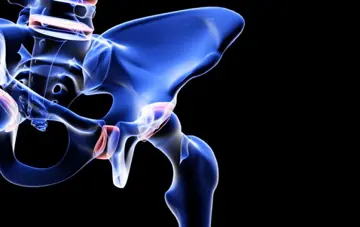

وضعیت ذهنی مردان پس‌از جراحی مفصل ران

مردانی‌که پس‌از جراحی مفصل ران(Hip) به‌هوش می‌آیند درمقایسه با زنان، اغلب مشکلات شناختی و مرگ‌و‌میر بالاتری طی ۲۲روز اول دارند.